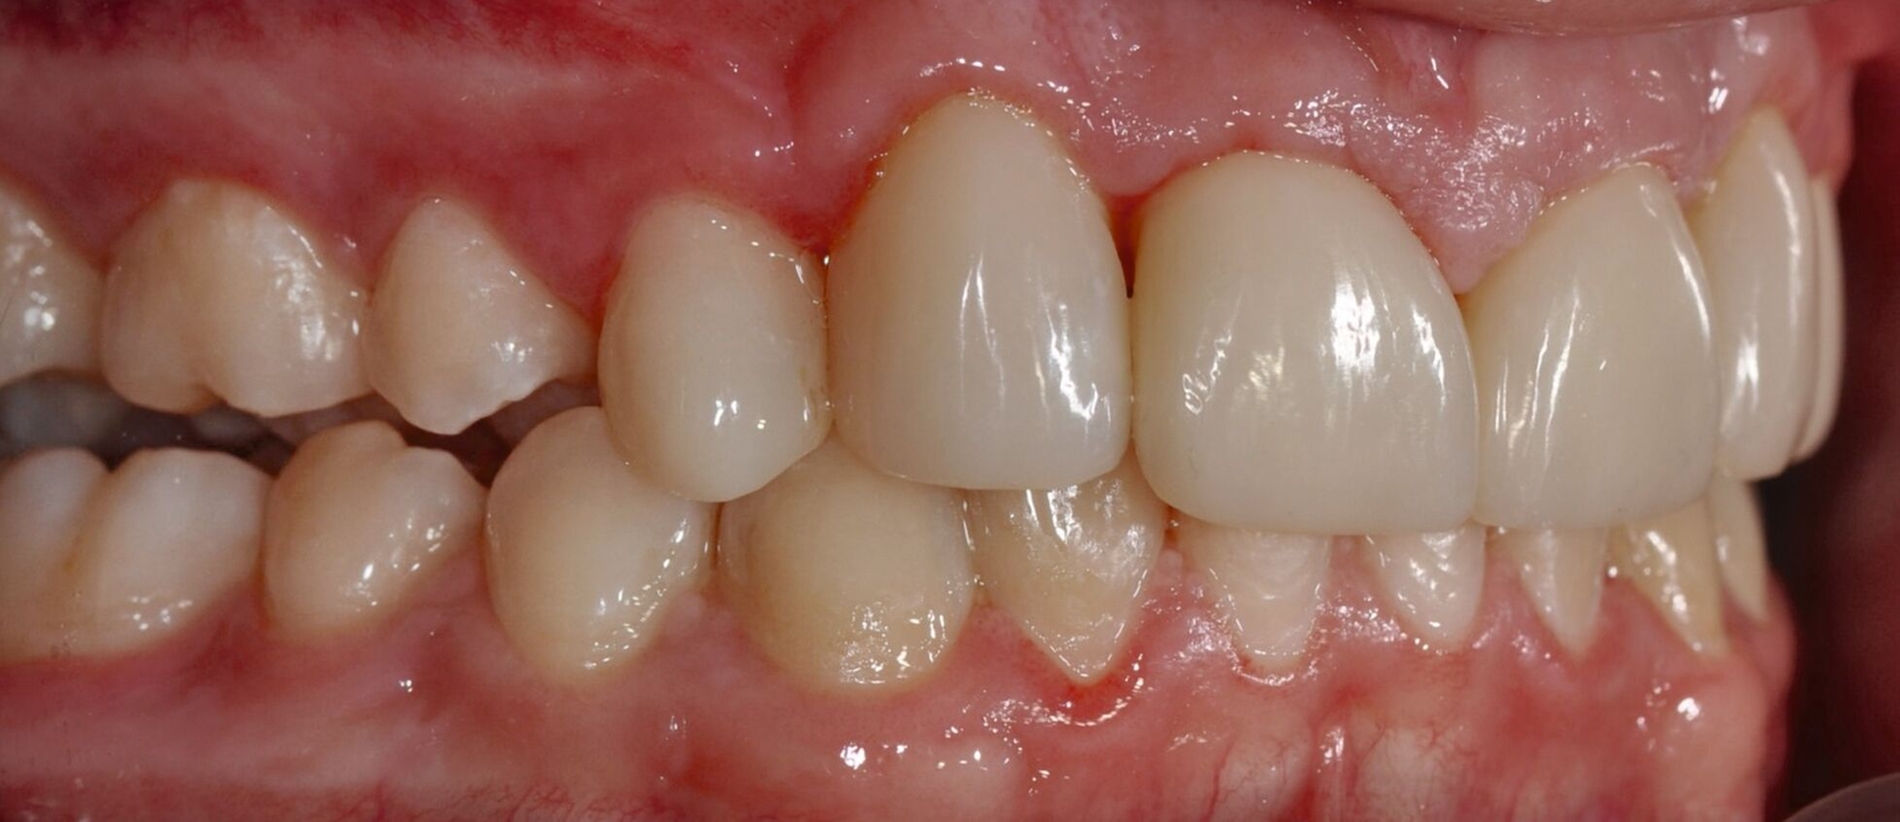

Bei der Erstvorstellung zeigt der Patient ein ausgeprägtes Diastema mediale sowie Restlücken und Asymmetrien im Oberkieferfrontzahnbereich nach kieferorthopädischer Therapie alio loco (Abbildung 1). Aufgrund mangelnder Adhärenz konnten nicht alle kieferorthopädischen Behandlungsziele erreicht werden, was insbesondere aus ästhetischer Sicht Herausforderungen für den restaurativen Lückenschluss mit sich bringt. Erschwerende Faktoren sind die Verschiebung der Mittellinie, die Achsenneigung der Zähne 13, 12, 22 und 23 sowie die inhomogene Lückenverteilung mit ungleich verteilten Lückengrößen (Abbildung 2). Eine erneute kieferorthopädische Korrektur lehnt der Patient allerdings ab. Subjektiv empfindet er insbesondere das kindliche Erscheinungsbild der lückig stehenden, kurz und klein wirkenden seitlichen Schneidezähne als störend. Ziele der Behandlung sind eine präventionsorientierte, ästhetisch-funktionale Rehabilitation des Oberkieferfrontzahnbereichs und eine Harmonisierung des dentofazialen Erscheinungsbildes.